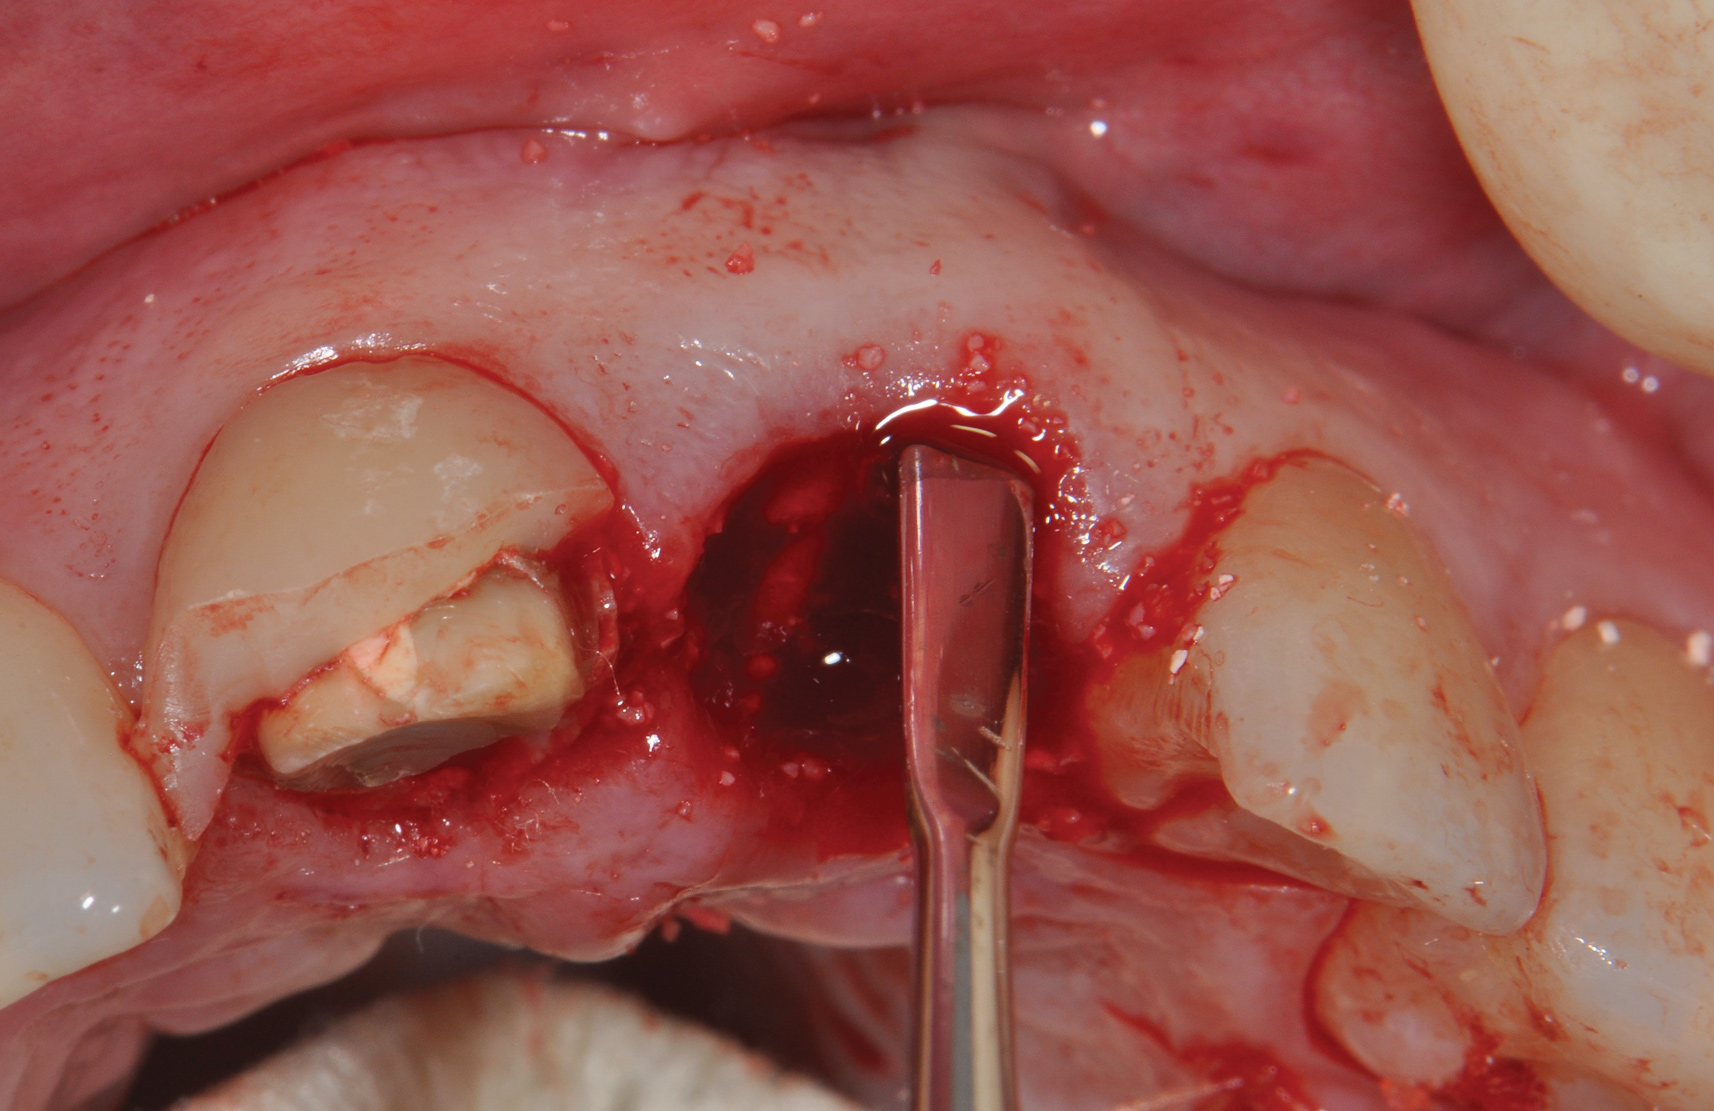

The patient, a healthy 45-year-old nonsmoking woman (American Society of Anesthesiologists [ASA] II), presented with a failed maxillary central incisor due to severe internal-external root resorption (Figure 1). She had a high esthetic risk profile based on 12 presenting esthetic risk factors (key No. 1), including a high lip line, high esthetic expectations, and adjacent teeth that had been restored (Figure 2).Site-specific CBCT (Carestream CS 9300, Carestream Dental, carestream.com) noted a thick intact buccal plate and a class 1 sagittal root position (Figure 3 and Figure 4). Preplanning with a bone-level 4.1-mm diameter x 14-mm long implant (Straumann Bone Level Roxolid® SLActive, Straumann, straumann.com) assured a 3-mm buccal gap upon placement and a screw-retained position (key No. 2). Prior to placement, intact buccal and palatal walls were confirmed. Figure 5 shows palatal wall placement of the implant after minimally traumatic flapless tooth extraction. An anatomically correct surgical guide template was used to assure a screw-retained position and correct vertical depth of approximately 4 mm from the mid-buccal apical extent of the guide template, which correlated to 1 mm apical of the intact buccal plate (key Nos. 3 through 5). The two-unit (8-9x cantilever) fixed provisional was recemented post-surgery. The 3-mm buccal gap was grafted tightly with a low-substitution DBBM (Bio-Oss®, Geistlich Pharma, geistlich-na.com) (key No. 6), and a pouch was created with a Buser membrane instrument (Hu-Friedy, hu-friedy.com) from line angle to line angle as a mini full-thickness flap to the mucogingival border to accept a connective tissue graft (Figure 6). The connective tissue graft, 1-mm thick x 12-mm long x 7-mm wide (Figure 7), was harvested from the palate (key No. 7).

Fig 6. The 3-mm buccal gap was grafted tightly with low-substitution DBBM, and a pouch was created as a mini full-thickness flap to accept a connective tissue graft.

Figure 6